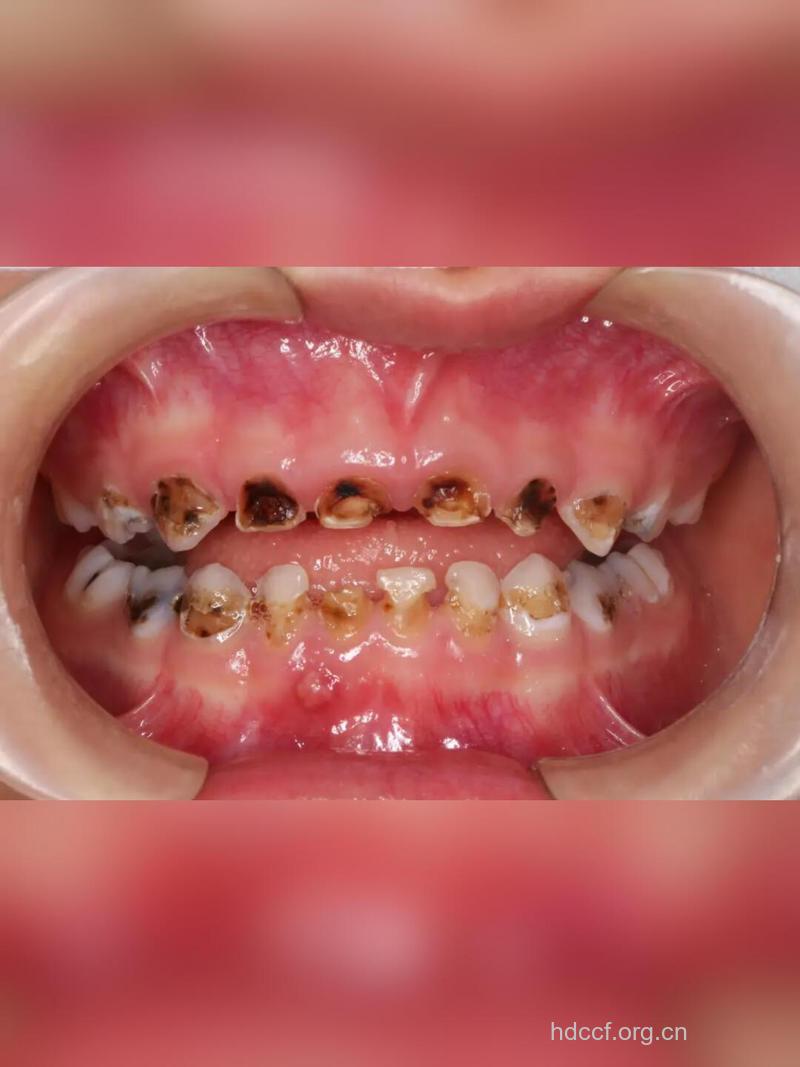

龋齿是多发生于青少年的,发生龋齿对患者造成的危害是比较多的,很多人不了解该病,所以也不知道怎么治疗。只有了解龋齿的种类,才能进行有效的针对性治疗。现在小编就为各位朋友详细介绍一下龋齿的症状表现。

有中龋、深龋的特点,及龋损着色浅,质湿软,易被挖匙除去等特点。

有急性龋的特点。此外龋损发生在大多数牙齿及牙面,甚至涉及可以自洁的牙面。患者多有全身疾病,如长期慢性病,或并发唾液分泌减少疾病(因头颈部放射治疗后引发的猖獗性龋又称为放射性龋)。